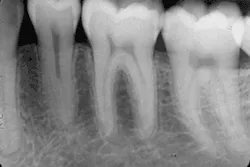

Figure 1 shows how I enhanced the carious lesions in these periapical X-ray images to make them more visible. The technique to acquire the image is no different than with conventional X-ray techniques. The real challenge is to take the time to understand the elements necessary to make the transition: computers, networking, terminology, and electronic image processing (EIP). I hope the articles in this series will make your transition easier and more rewarding.